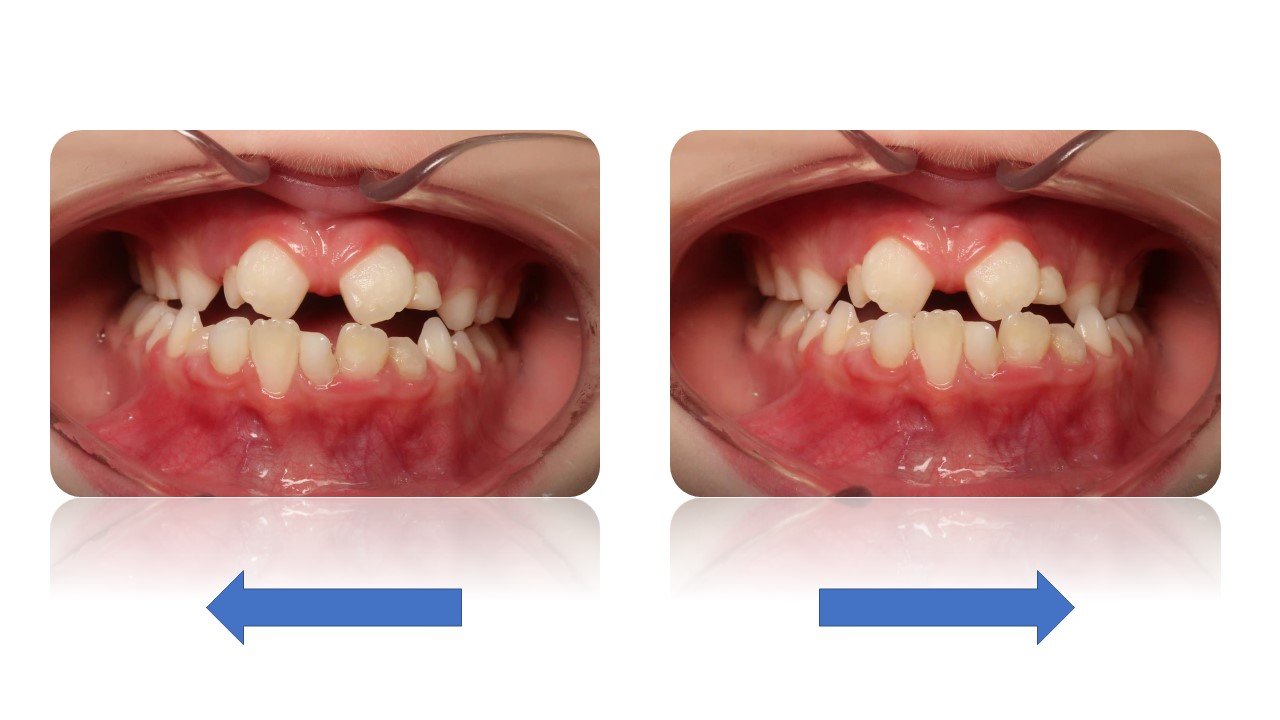

La Classe II Subdivision

La classes II subdivision fonctionnelle est la conséquence d’une mastication préférentielle voir exclusivement unilatérale. Cette dysfonction engendre alors une bascule du plan d’occlusion dans le plan frontal mais également dans le plan vertical et sagittal.

L’orthodontie systémique permet d’appréhender cette pathologie par l’analyse des latéralités mandibulaires (AFMP).

Le traitement qui en découle est donc fonctionnel et stable car il permet une réorientation du plan occlusal, symétrisant ainsi les AFMP et donc la mastication.

C’est donc la fonction qui joue le rôle de contention des traitements systémiques.